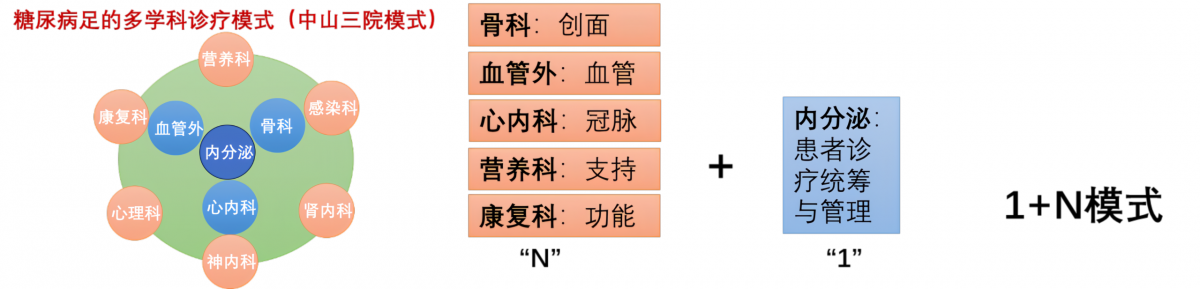

★糖尿病足病中心

糖尿病足的治疗涉及血糖调控、血管疏通、创面修复等多个环节,面对糖尿病足这一危重并发症,医院整合内分泌、血管外科、创伤骨科、烧伤科、介入科等多学科力量,成立糖尿病足病中心,提供预防、诊断、治疗、康复的“一站式”闭环管理。

通过全方位血管神经评估、阶梯式治疗方案(如血流重建、创面修复、骨搬移等),并建立急诊救治绿色通道,最大程度降低截肢率,保全患者肢体功能与生活质量。

核心技术:

◆下肢血管及神经评估(ABI、超声、CTA、10g单丝,神经传导速度等)

◆创面分级评估及治疗(负压吸引、生物敷料等)

◆血流重建(球囊扩张、支架置入等)

◆保肢与修复(骨髓炎清创、骨搬移、皮瓣移植)